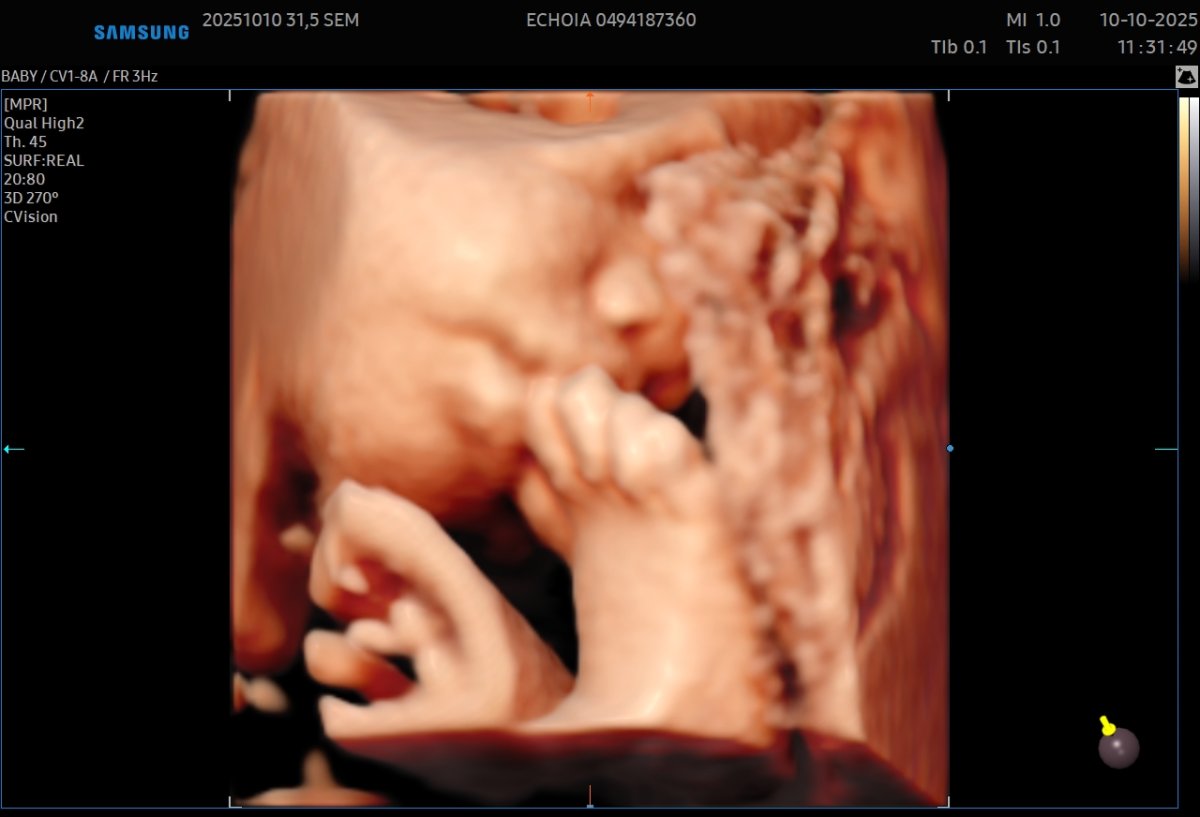

Gallerie de photos